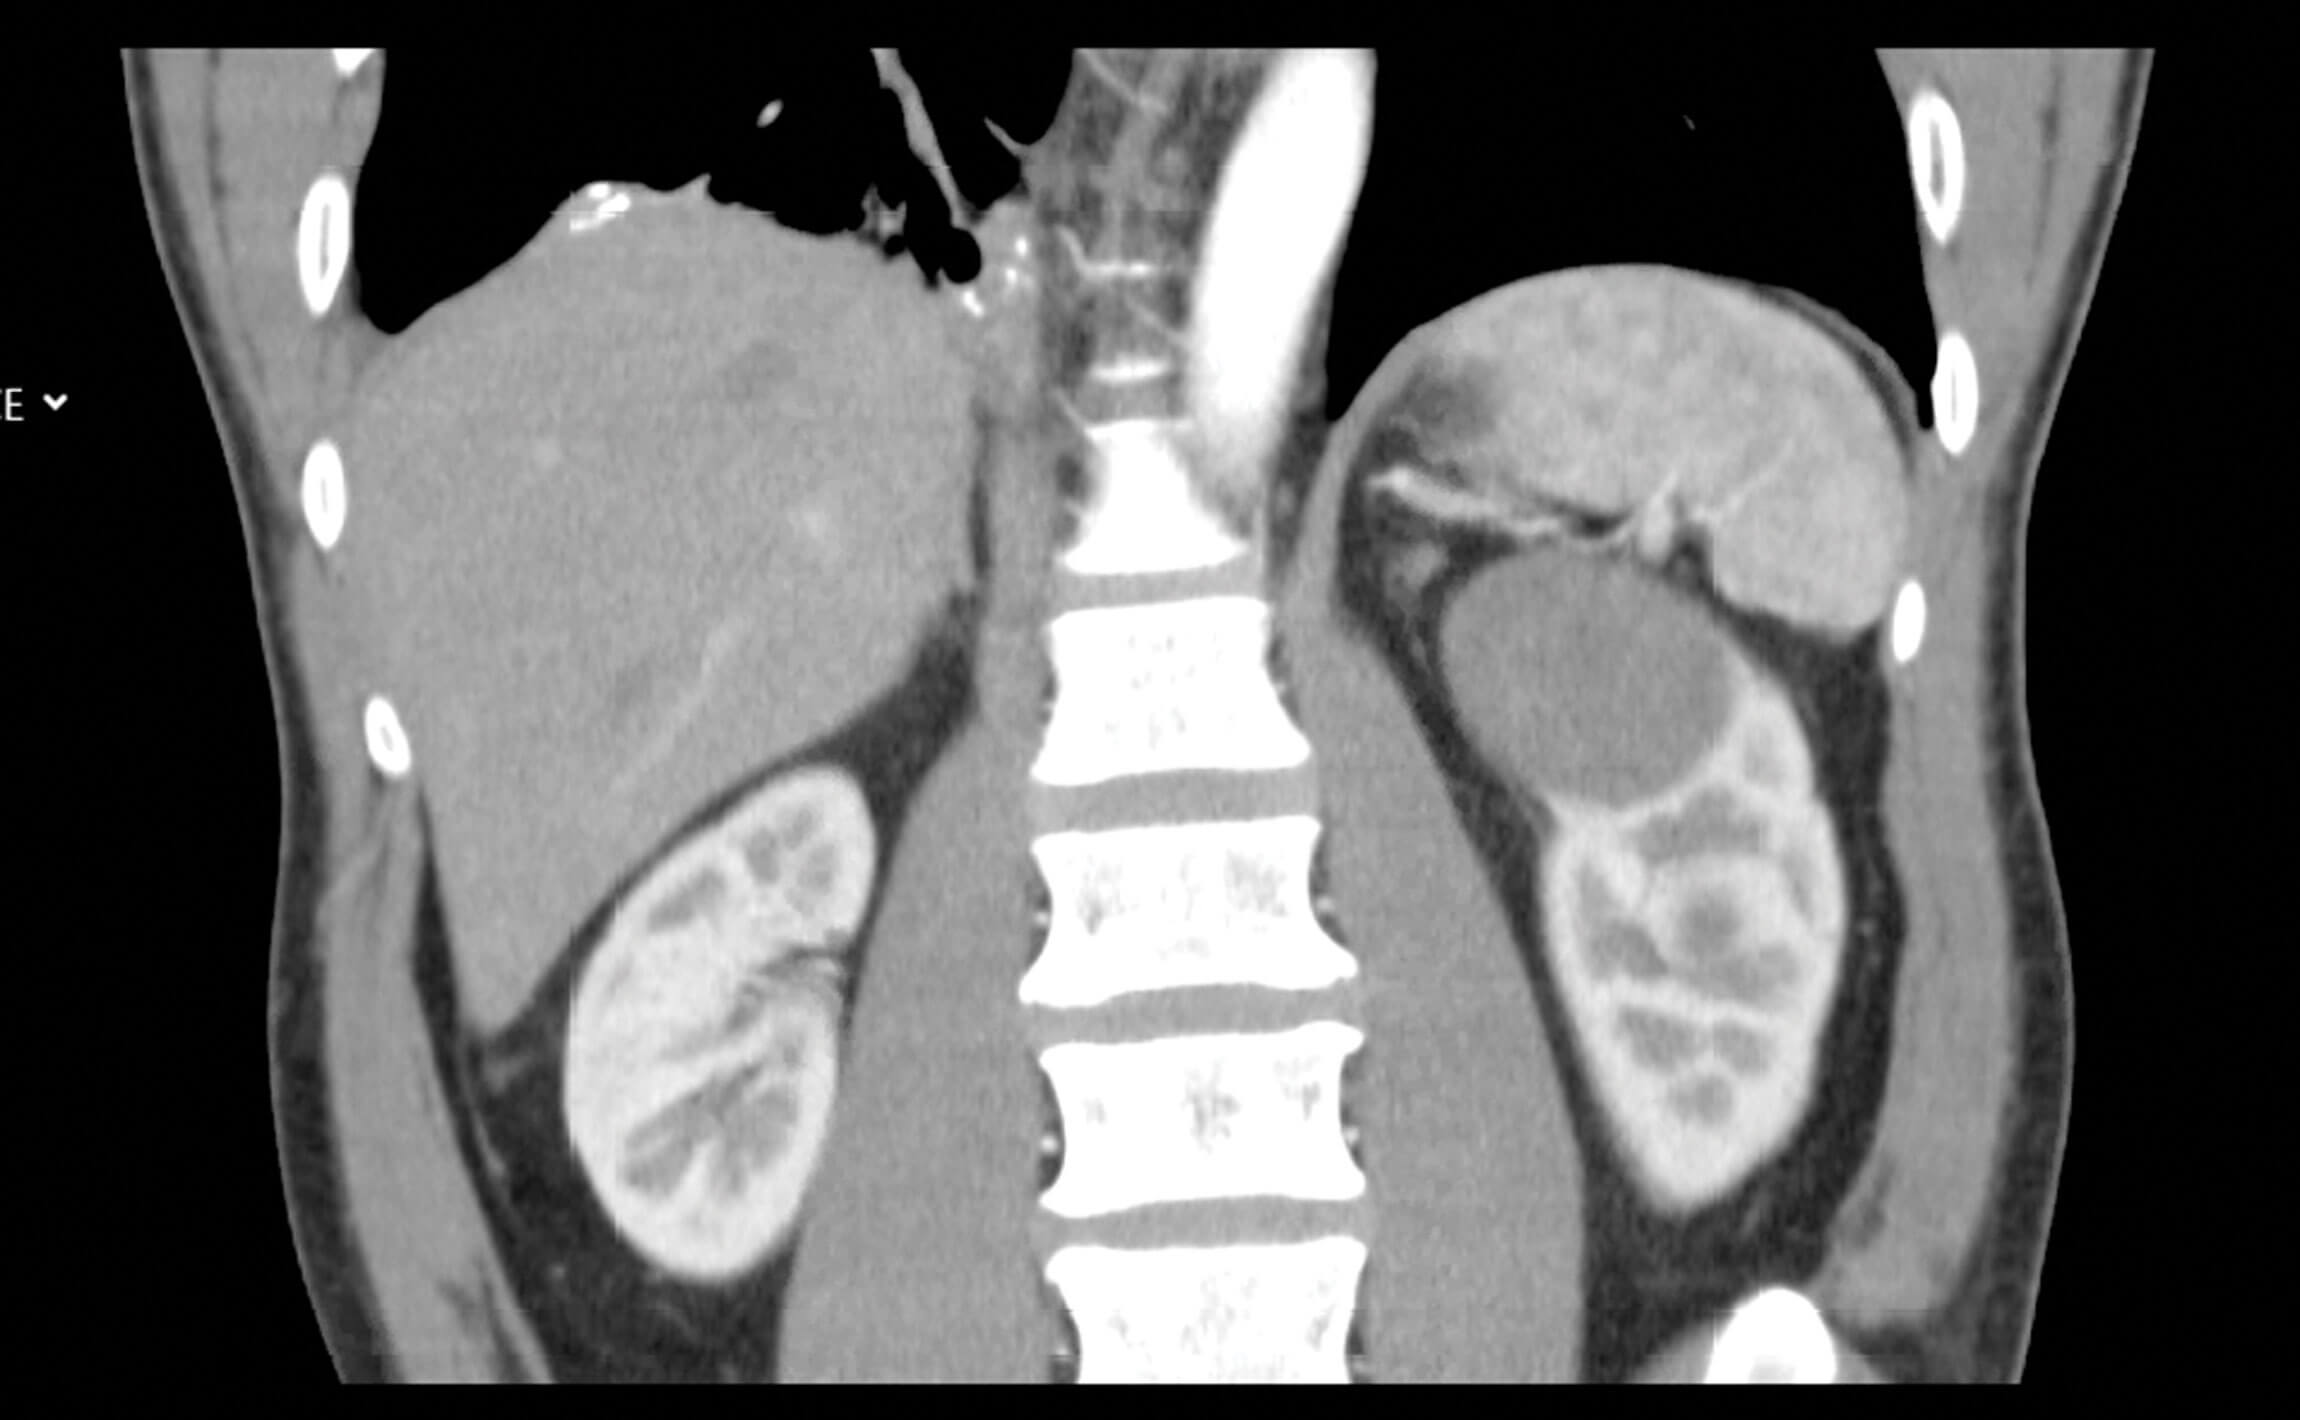

Our patient is a 42-year-old man who was referred to the department after a CT scan found two left sided renal masses suspicious for papillary RCC, an interaortacaval lymph node mass that appeared to be a separate pathology (later found to be a paraganglioma) and multiple bone lesions in his iliac joints and right seventh rib (Figure 1).

Figure 1: Presenting CT arterial portography of the patient, post contrast coronal,

note the bland looking homogeneous tumour in the upper pole of the left kidney.